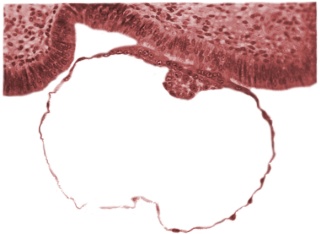

IntroductionStage 4 is reserved for the attaching blastocyst that is adhering to the endometrial lining of the uterus. The attaching process is called adplantation and heralds the onset of implantation. Stage 4 embryos have an estimated postfertilization age of approximately 6 days. Read more... |

Embryo attached to an endometrial cell cultureMore Figures... |